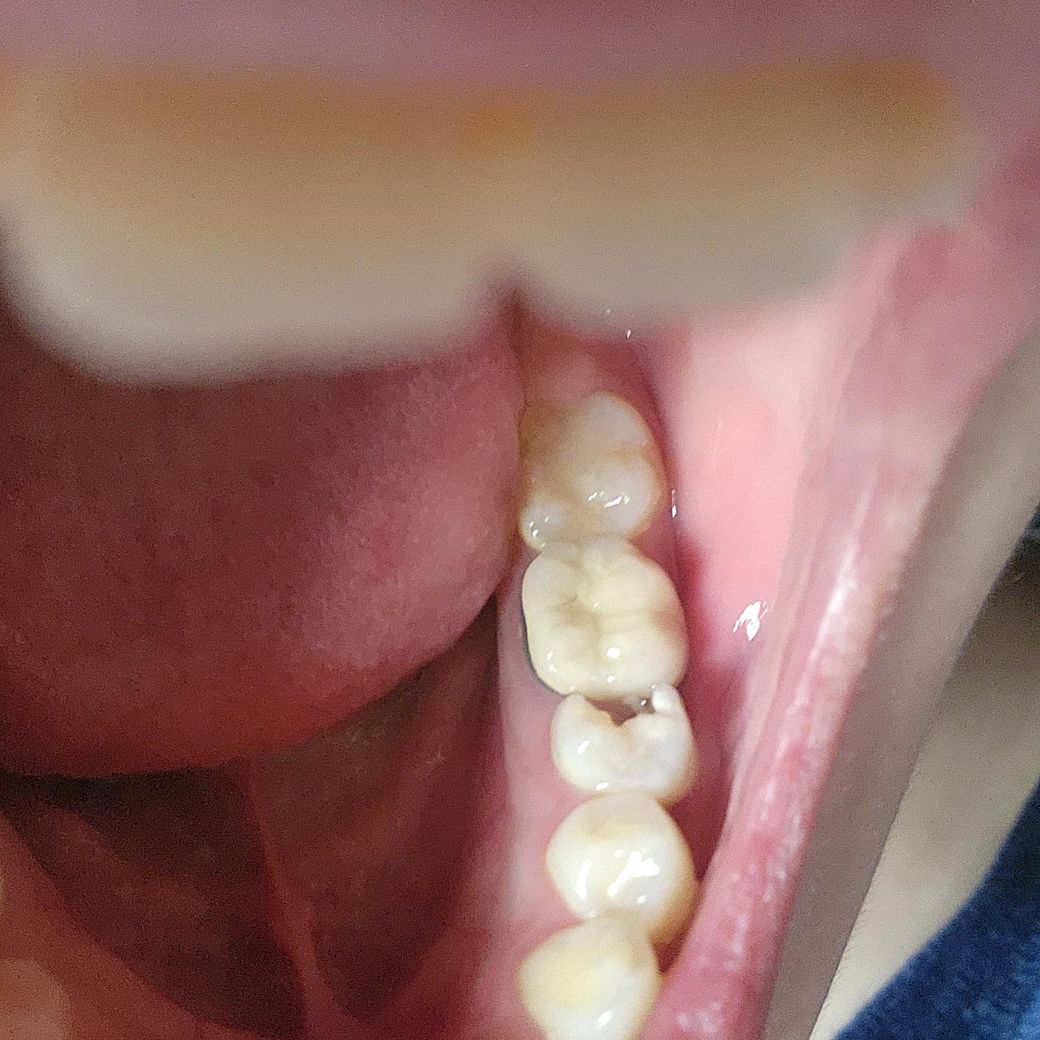

치아에 구멍이 났는데 까만색은 안보여서 충치는 아닌거같은데...이물질이 들어갈때마다 치실로 빼주고있긴한데..잇몸도 부운것처럼 아파요ㅠ

더군다나 구멍난 곳 위?쪽이 신경치료한부분이기도 해서...암튼 이정도면 심각한 수준인가요...?ㅠ 의사쌤 말로는 양치를 잘해도 충치가 잘 생기는 약한 치아라는데...ㅠ

사진은 충치가 많이 생긴것으로 보입니다.

충치가 생긴 치아는 충치를 치료하는것이 좋으며 사진으로 봤을 경우 충치가 신경까지 생겼을 가능성이 높아 보입니다.

네 너무 확실한 충치입니다. 치아 더 깨져나가기전에 치과가서 처치 받으시기 바랍니다..

충치입니다. 신경치료 가능성도 높아 보이는데요.

현재 치아에 구멍이 난 상태도 충치로 인해 치아가 파손된 것으로 이 경우 빠른시일내에 치과에 방문하여 치료를 받길 권하며, 현재 구멍이 난정도가 커서 크라운 치료가 필요로 될 가능성이 높습니다.